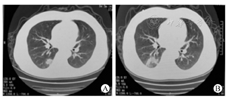

例2 2020年1月17日最高体温37.8 ℃,后体温逐日下降,2020年1月18日最高体温37.1 ℃,2020年1月19日最高体温36.9 ℃,受者自我感觉可。2020年1月20日再次发热,最高体温38 ℃,出现少许干咳,复查胸部CT对比2020年1月17日CT提示双肺感染性病变,右肺上叶病灶较前吸收,两肺下叶病灶较前进展,余大致同前(图2)。治疗方案调整同例1后,2020年1月21日起受者未再发热。2020年1月23日2019-nCoV RNA检测回报,2例受者均双阳性:COVID-19核壳蛋白基因阳性、2019nCoV开放阅读编码框lab阳性。根据国家传染病法规定,转至指定医院继续治疗。后该受者自我感觉无异常,每日尿量约2 500 ml,血肌酐约130 μmol/L。复查胸部CT提示感染灶已基本吸收,复查2019-nCoV RNA阴性,2020年2月8日康复出院。

肾移植受者长期使用免疫制剂在有效降低机体排斥反应的同时也极大程度的减低了机体对病毒、细菌等病原体感染的免疫能力,肺部感染是肾移植术后主要的感染类型之一,具有起病隐匿、进展快、病情严重等特点[5,6]。本研究2例肾移植受者于2020年1月14日出现COVID-19的初期症状均是发热(中低热),无咳嗽咳痰,饮食、睡眠、精神均可,受者自我舒适度可,胸部CT为双肺多发的斑片状、片状磨玻璃阴影。2020年1月20日均症状加重,CT提示双肺感染进展,新发病灶主要以双肺中下叶为主。其中例1快速出现低氧血症,CT出现大片状毛玻璃影。例2的临床表现、CT改变与报道的COVID-19发病过程及影像学改变高度相似:以发热为起病表现,1周后出现呼吸困难和/或低氧血症,病情进展后两肺多发磨玻璃影。